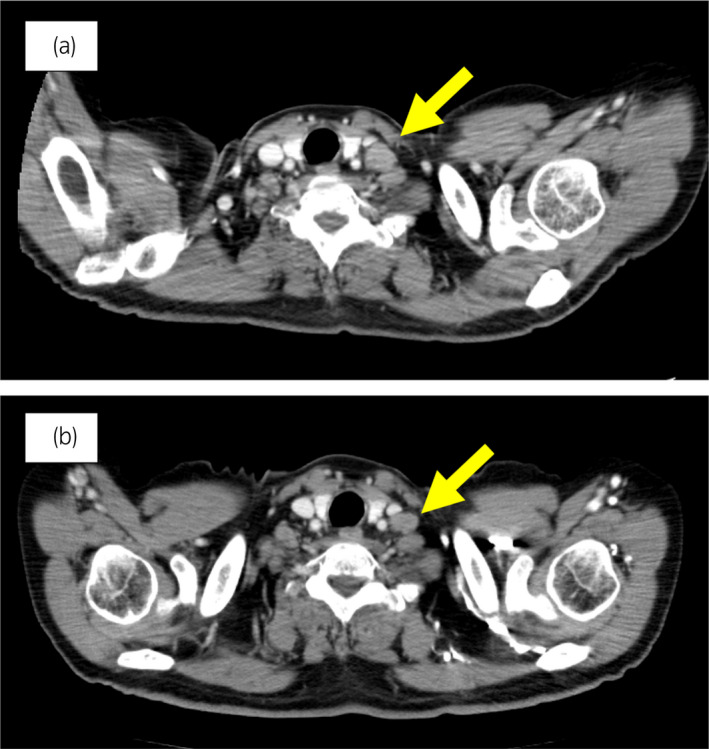

圖 3:案例 1. 開始使用奧拉帕尼之前和之后 3個月的鎖骨下淋巴結(jié)轉(zhuǎn)移的 CT 圖像。 (a) 治療前和 (b) 奧拉帕尼治療后 3 個月。 黃色箭頭顯示轉(zhuǎn)移淋巴結(jié)。